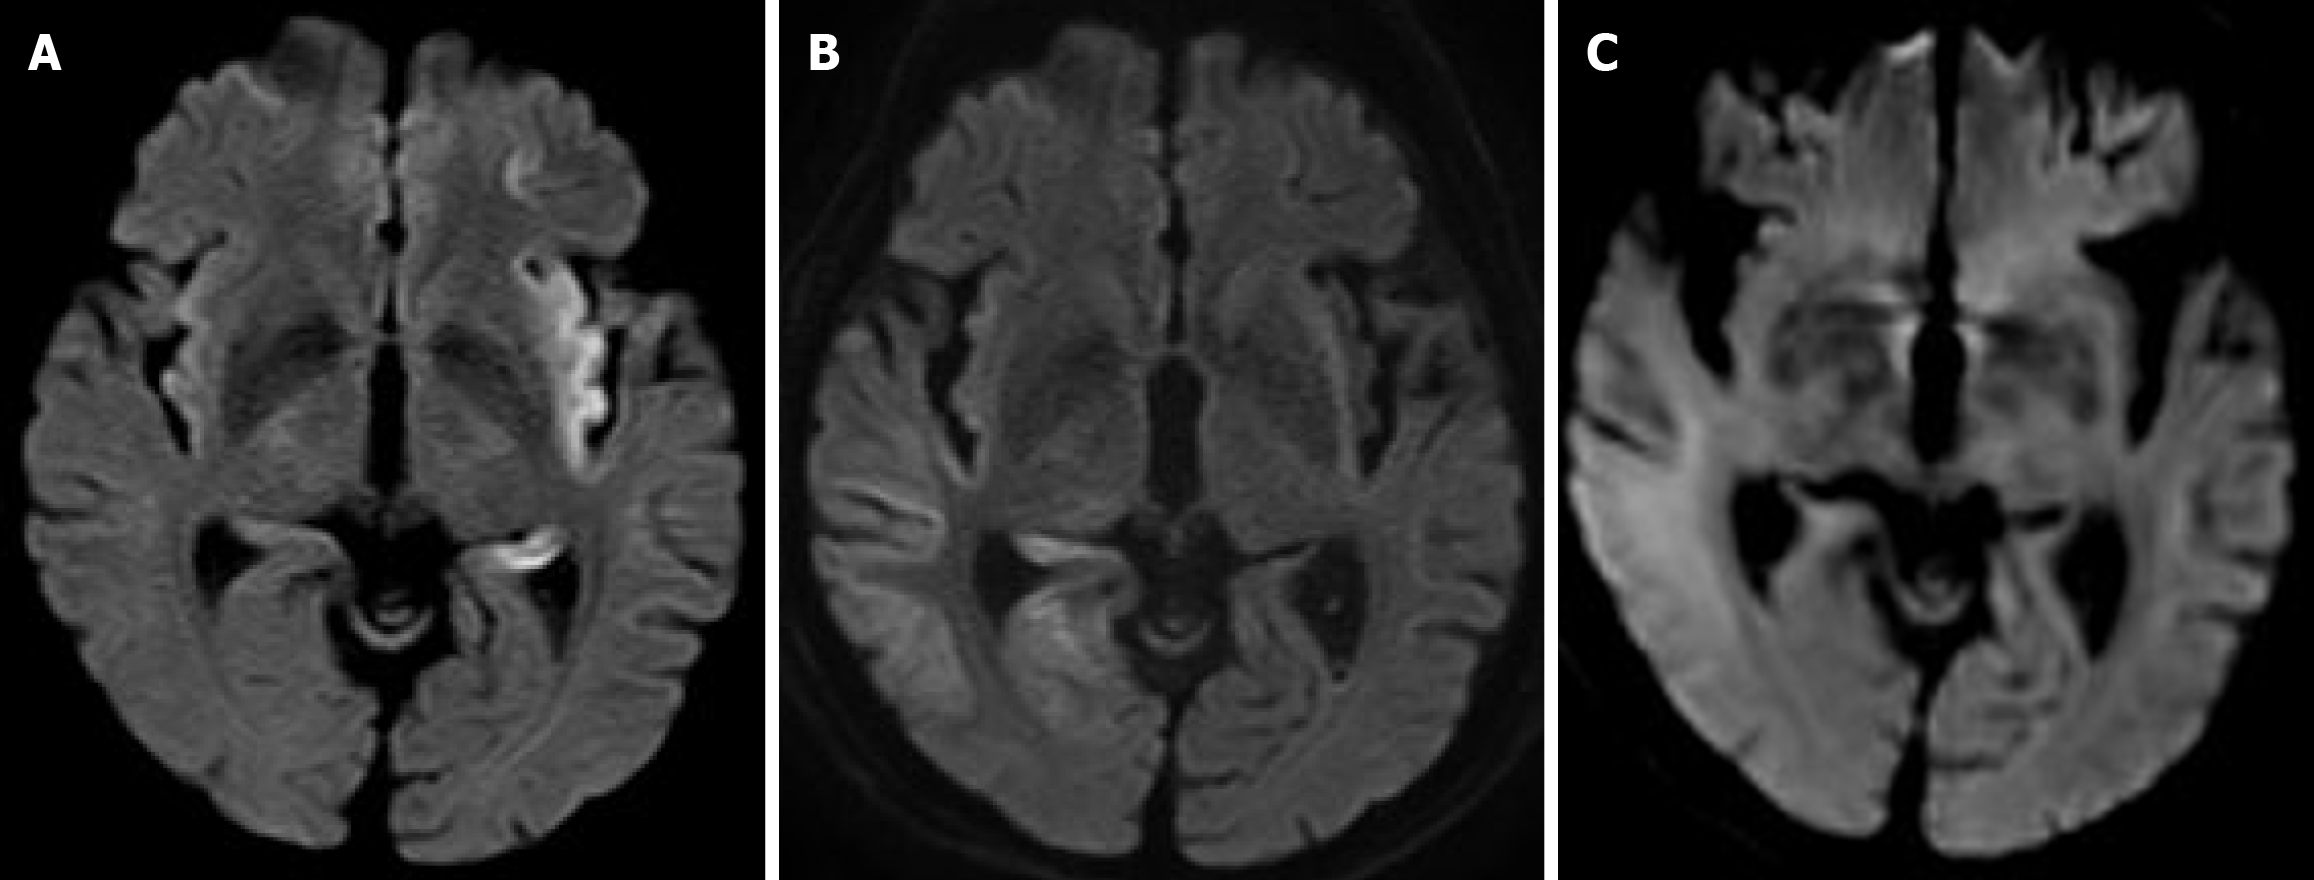

Figure 1 Diffusion-weighted image, magnetic resonance imaging.

A: On hospital day 3, a high-intensity area between the left temporal lobe and insular cortex was confirmed; B: On hospital day 48, a high-intensity area around the right temporal lobe was newly confirmed; C: On hospital day 117, no new recurrence was confirmed.